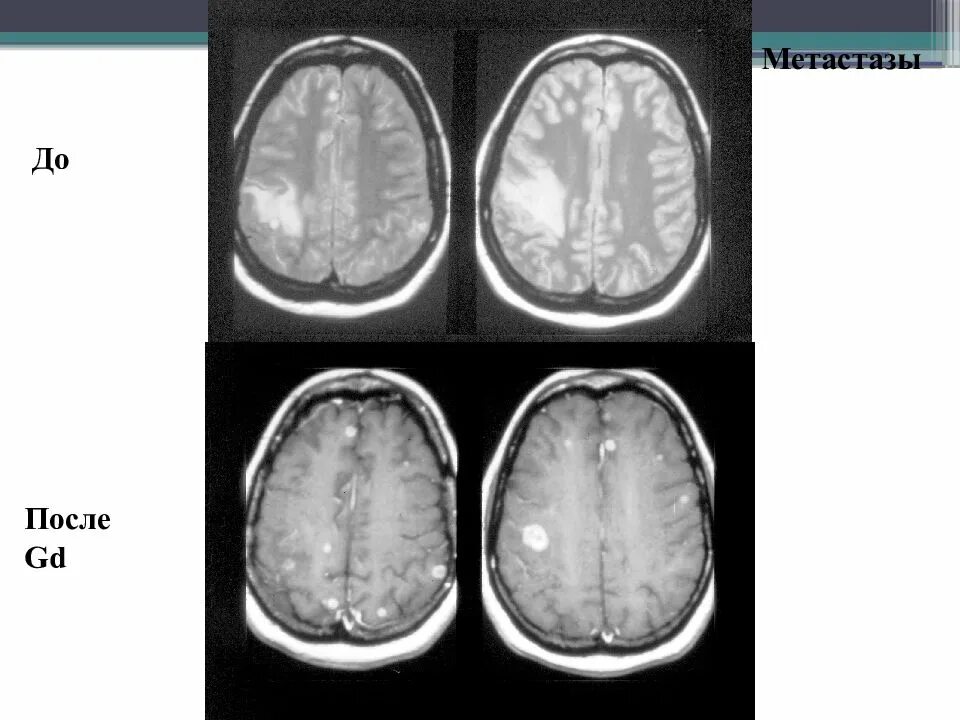

Метастазы головного мозга кт